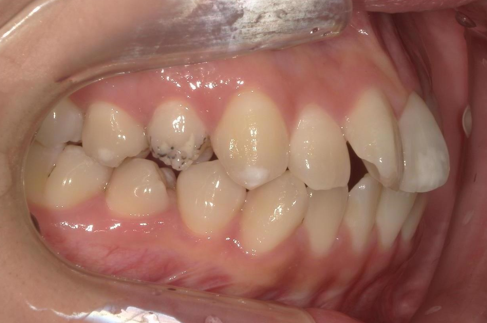

年齢 20代女性

主訴

上顎前突

前歯叢生

治療期間 2024年3月~25年12月

矯正種類 マウスピース矯正(クリアコレクト)

AFTER